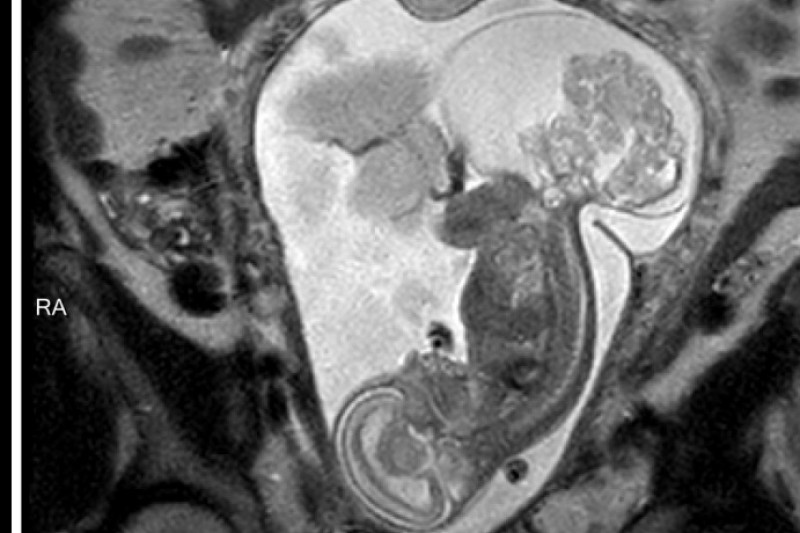

At 20 weeks we came to Houston for several tests including MRI, Ultrasounds, Echocardiograms, and meetings with the specailists at both Houston hospitals. At one hospital we were strongly encouraged to terminate the pregnancy due to the extremely large size of our baby's tumor and the risks to my health. Texas Children's gave us a more positive yet realistic option of having Open Fetal Surgery to remove a large portion of Lynlee's tumor to try to save her. They told us she had a 50% chance of making it with the surgery. Jeff and I were in agreement that termination was not an option and we wanted to give Lynlee a chance at life by going with Texas Children's and having Open Fetal Surgery.

On March 7th at 23 weeks 5 days I was taken into emergency Open Fetal Surgery because Lynlee's turmor was taking the majority of her blood supply and causing her to go into cardiac failure. The doctors cut me open a little larger than a C-Section and removed my uterus. They then made a very large incision in my uterus to access Lynlee and to attempt to remove the tumor. The tumor was so large they had to puncture the fluid filled part and then cut out the vascular part of the tumor. The doctors were successful in removing 90% of the tumor. It was a shock to Lynlee's system so they did have to help restart her heart and give her a blood transfusion. Once she was stable they put her back in and sewed up my uterus and abdomen. Then it became a wait and see game. The next few days were very critical and I remained in the hosptial for a week. Lynlee slowly recoved from the invasive surgery and began having a normal heartbeat.